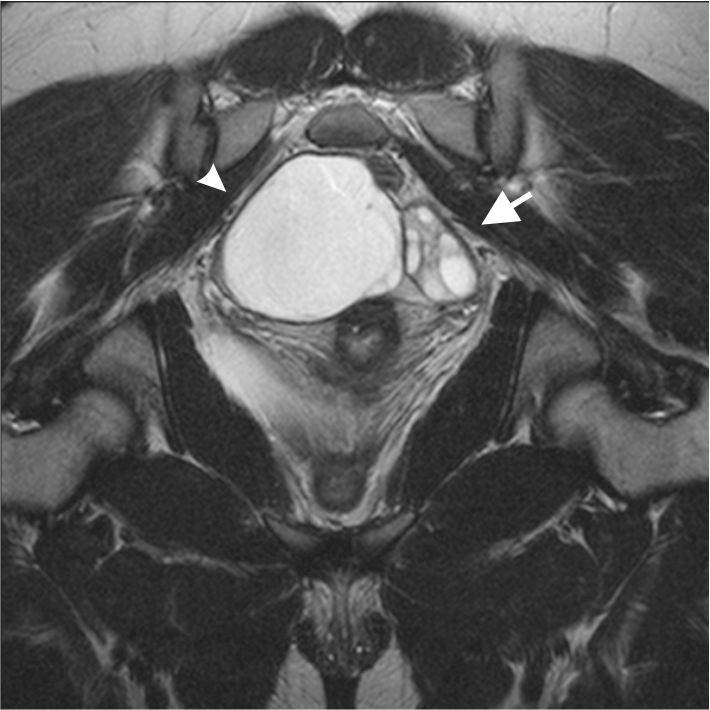

- Термин « замороженный таз » является не официальным медицинским термином, а неофициальным состоянием, означающим, что органы малого таза плотно сращены друг с другом из-за глубоко инфильтрирующего эндометриоза; и этими органами, как правило, являются прямая кишка, мочевой пузырь и мочеточники, матка и даже толстая и тонкая кишка.

- Трубы, яичники и связки таза также могут быть поражены.

- Критерием «глубокого инфильтративного эндометриоза — DIE » (официальный медицинский термин) является наличие твердого эндометриоза, проникающего более чем на 5 мм в дно таза, который обычно представляет собой краеугольный камень прилежащих органов.

- Органы, плотно спаянные с помощью «спайков», имеют нервы, которые развиваются внутри этих спаек, способствуя боли, которая начинается при воспалительном процессе эндометриоза.

- УЗИ, особенно при подозрении на эндометриоз яичников («эндометриома»). Он также точен при определении стертого тупика.

Единственным официальным способом диагностики эндометриоза является окончательная хирургическая идентификация и удаление для биопсии фактической ткани эндометриоза. Это делается с помощью лапароскопии или, лучше, роботизированной хирургии, чтобы не только тщательно оценить внутреннюю часть живота/таза, но и одновременно предложить возможность хирургического лечения (иссечение эндометриоза и/или отделение слипшихся органов).